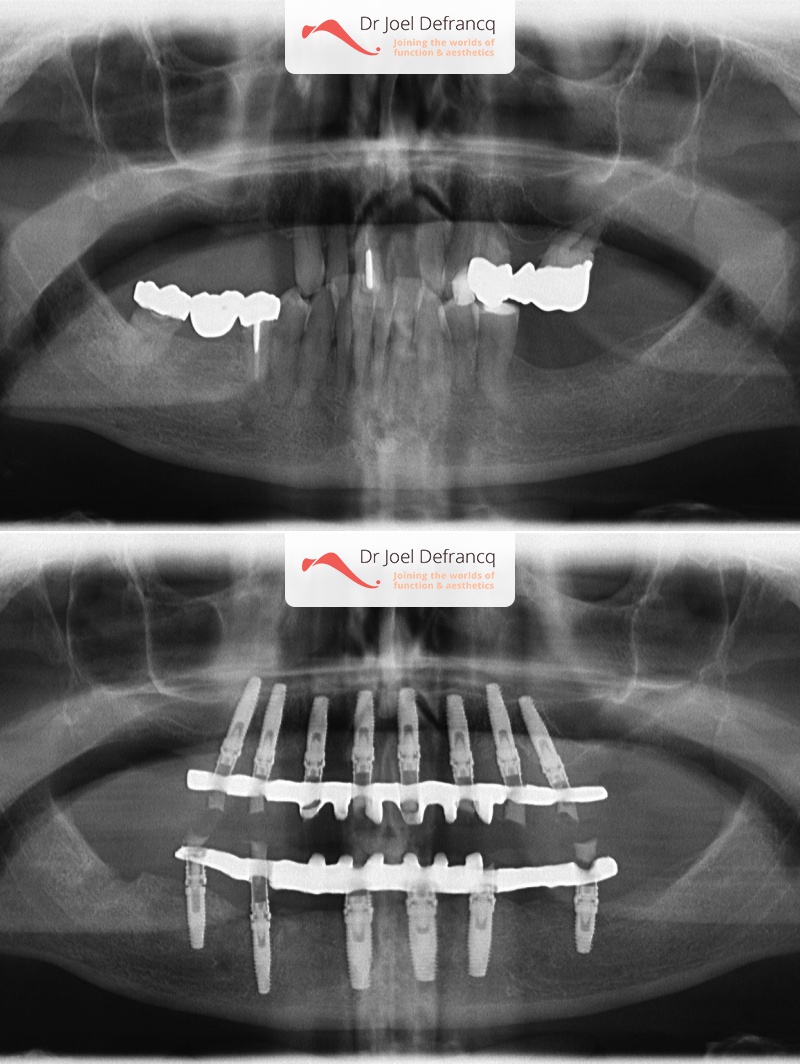

- Falende tanden. Immediate belasting op de implantaten (één week).

- Vaste tanden op implantaten (bovenkaak)

- Vaste tanden op implantaten (onderkaak)

- Begin tot einde in één week via onmiddellijke belasting der implantaten.